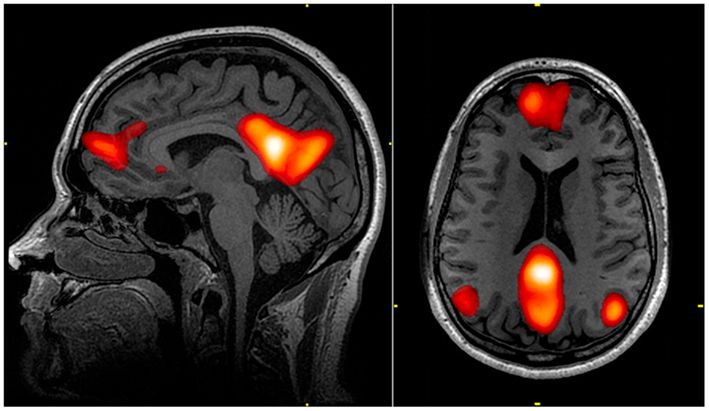

It’s down to something in our brains called the Default Mode Network or DMN.

Scientific investigation has now shown that our DMN takes over when we are undertaking familiar activities such as tying our shoelaces or, playing a musical instrument or, as in this case, driving a familiar route.